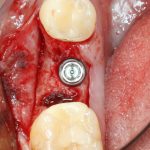

Рекомендации по установке имплантов. Для всех. Часть V.